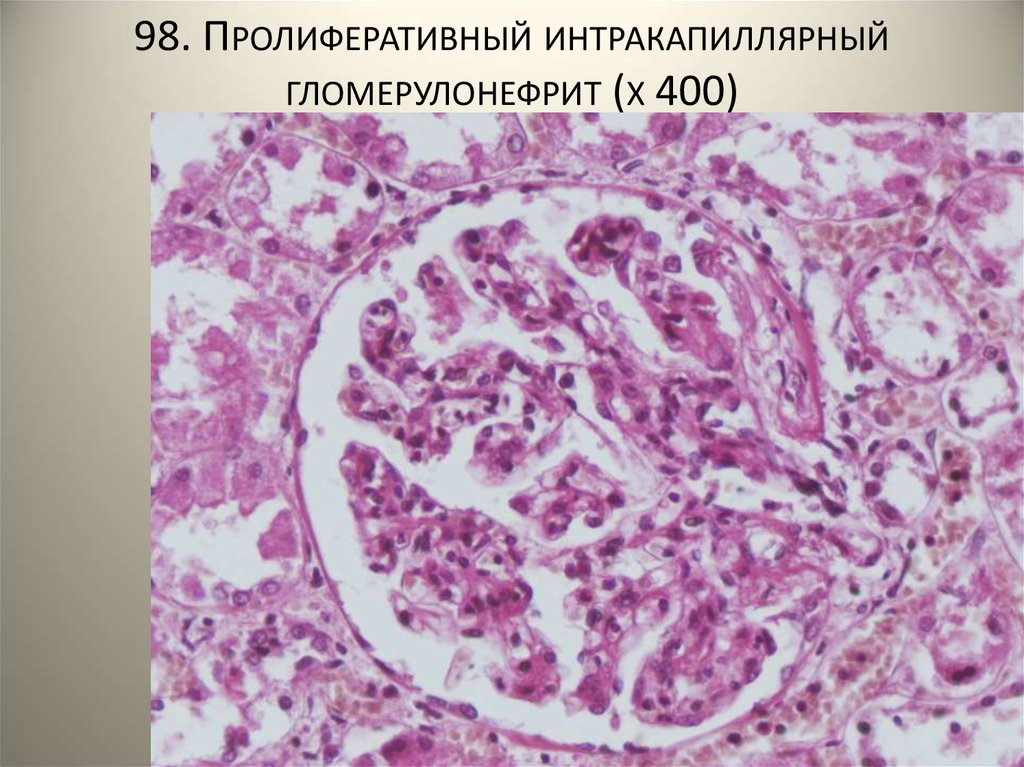

Механизм остро го диффузного гломерулонефрита